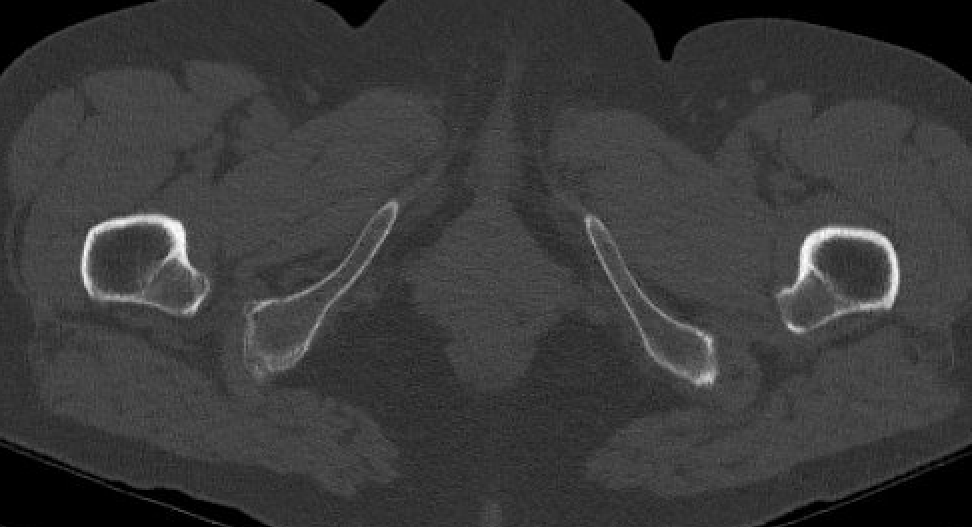

CT

IFI

IFIIFIIFI